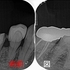

患者さんは20代女性

矯正中に来院して頂いた際には小さな虫歯だったのですが、

矯正が終わった頃には歯肉縁下まで入る大きな虫歯になってしまっていました。

それに伴い骨も大きく無くなっています。

今回のケースは、矯正治療で第2大臼歯も近心傾斜させてしまっており、上にレジンで立ち上げるスペースも無い為ヘミセクション(分割抜歯)を選択しました。

分割確認のレントゲン

ヘミセクション後 フルジルコニアクラウンを入れさせてもらったのですが・・・

クラウンを入れて2年半後にコアごとクラウン脱離

骨の所見を見ると、咬む力による問題+クラウンに強すぎる材料を使ってしまったここと推測

患者さんに謝り、もう一度根管治療からやり直させてもらいました。

ヘミセクションの際に自分がレジンコア作るべきだったと反省。。。